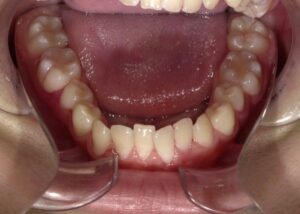

正面

- Before